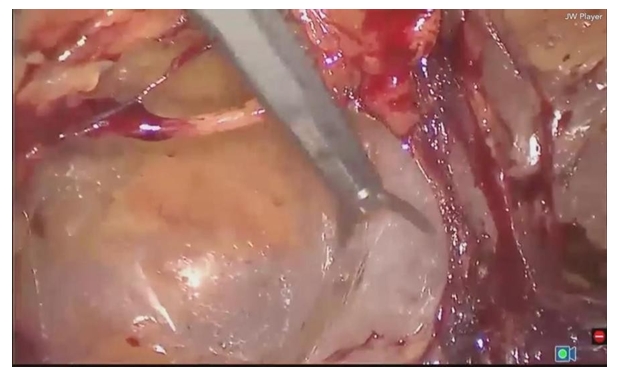

A feature of full extraperitoneal e-TER hernioplasty is that the entrance to the abdominal cavity is not performed, and all manipulations take place in the space created outside it (Fig. 5, 6). | Figure 5. Dissection in the extraperitoneal space |

| Figure 6. The mesh implant is placed in the preperitoneal space |